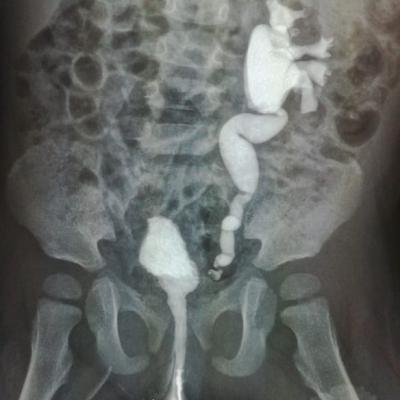

Здравствуйте.Ребенку 14.09.17г.р.сделали эндоскопическую коррекцию ПМР 4ст.второй раз ,хотя квота выписывалсь на сложную операцию.После коррекции ребенок стал мочиться еще реже и ухудшился ОАМ на четвертые сутки.